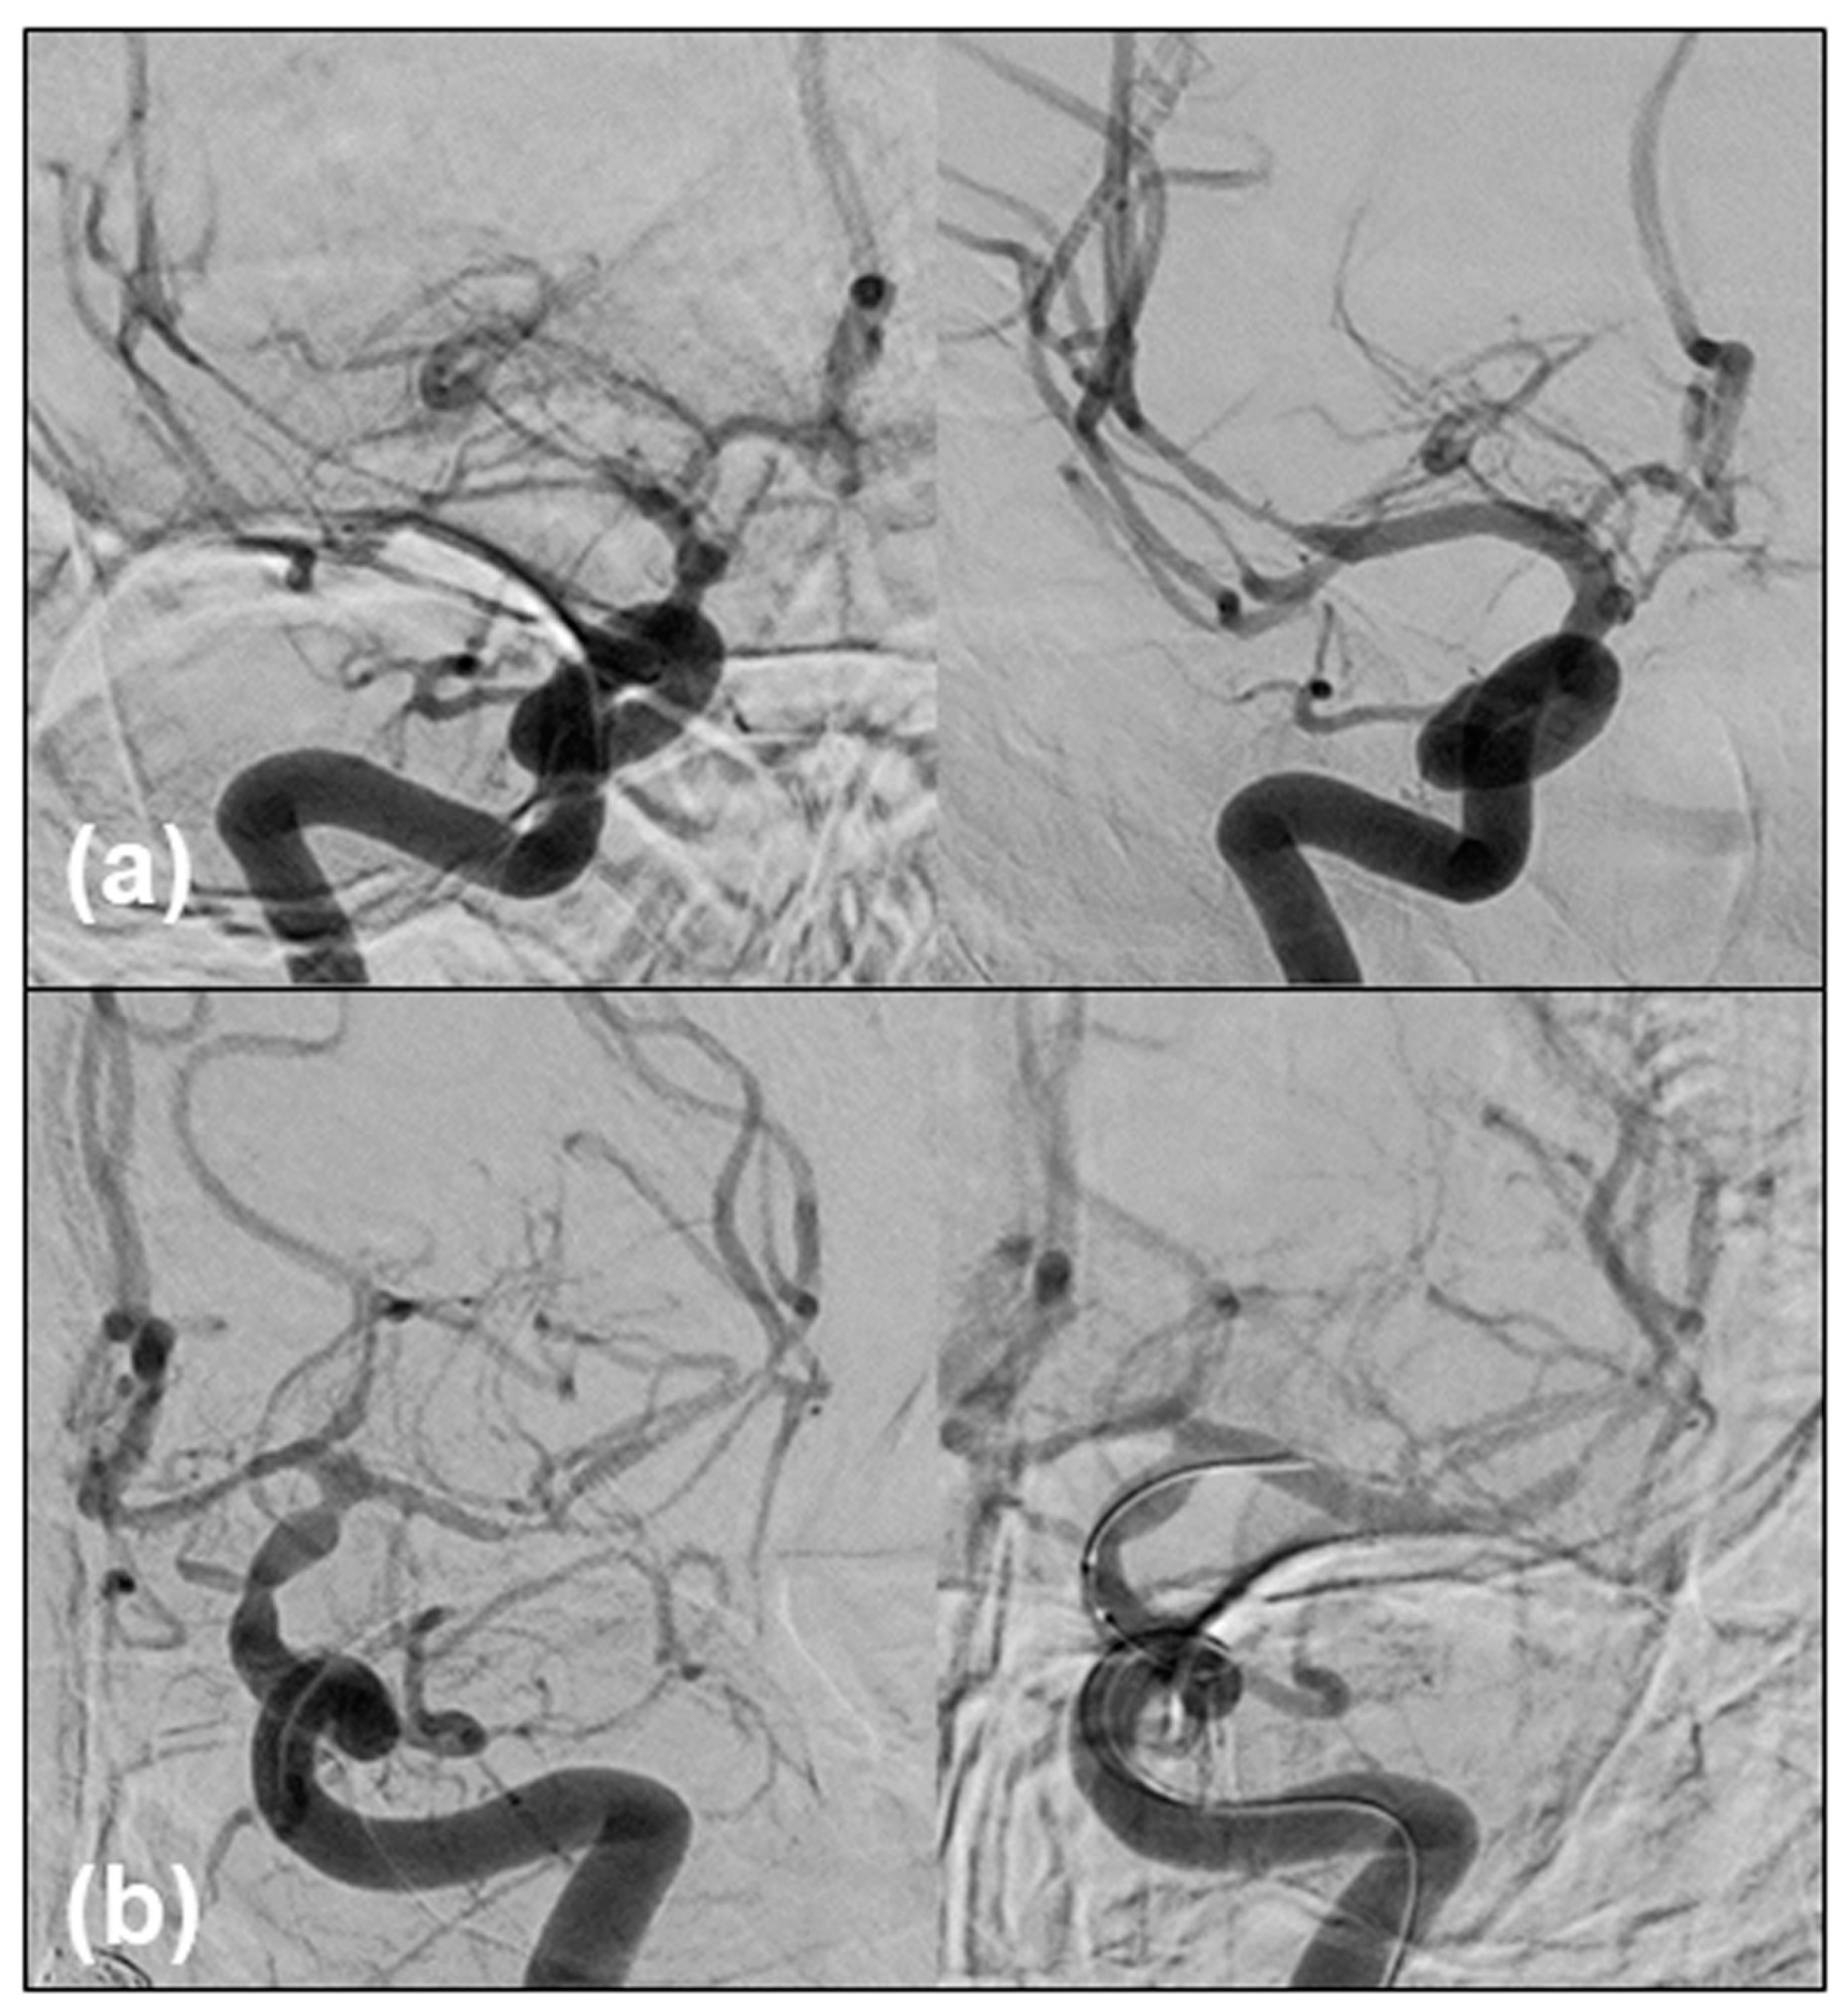

2. Case Report

2.1. Case Presentation

2.2. Contracting Case without Vasospasm